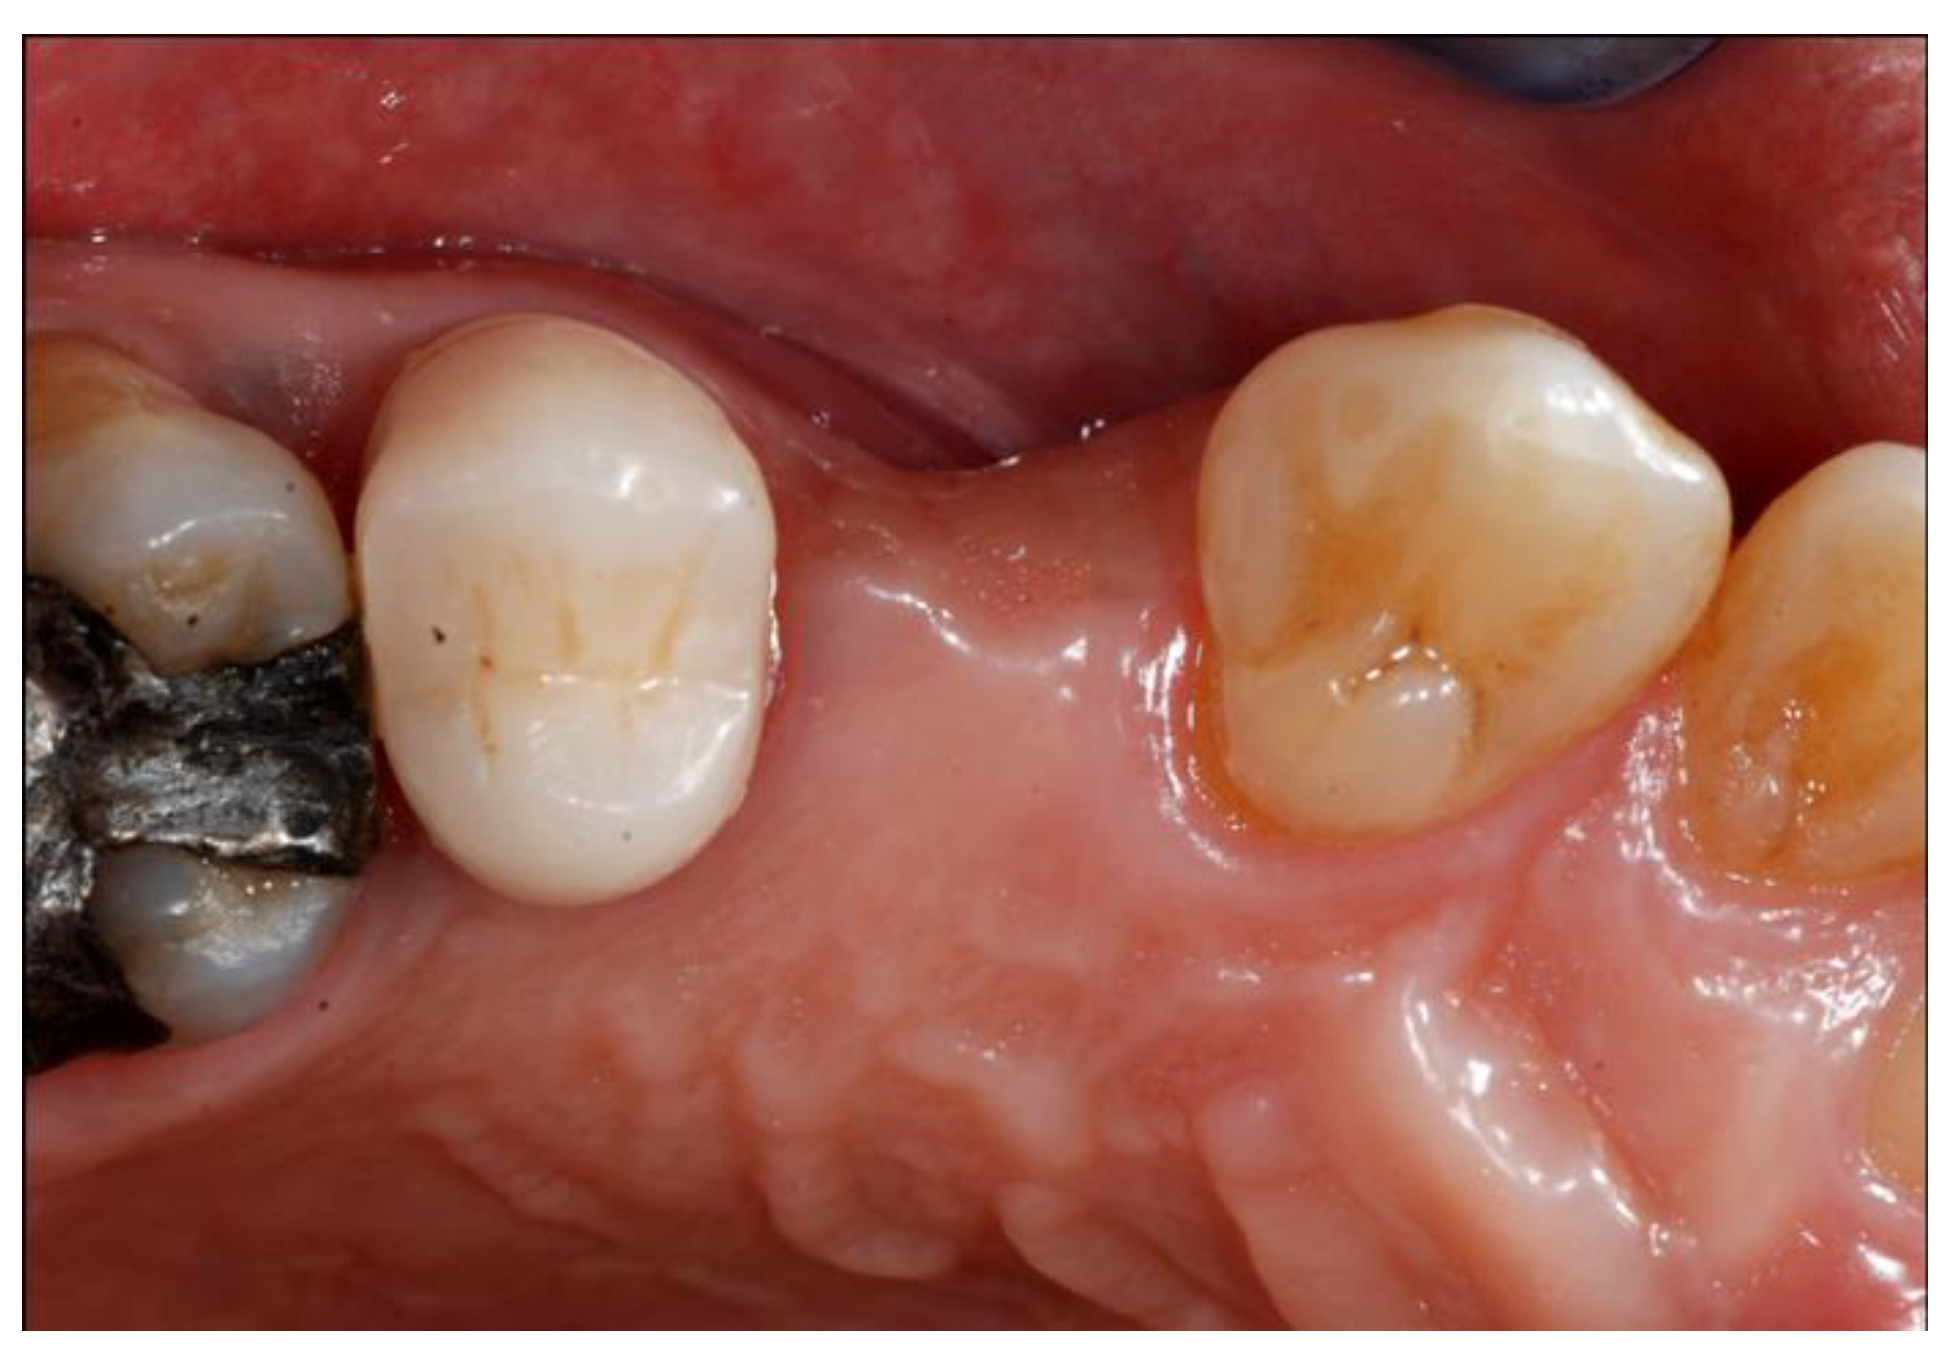

2.5. Re-Entry Surgery and Prosthetic Phases